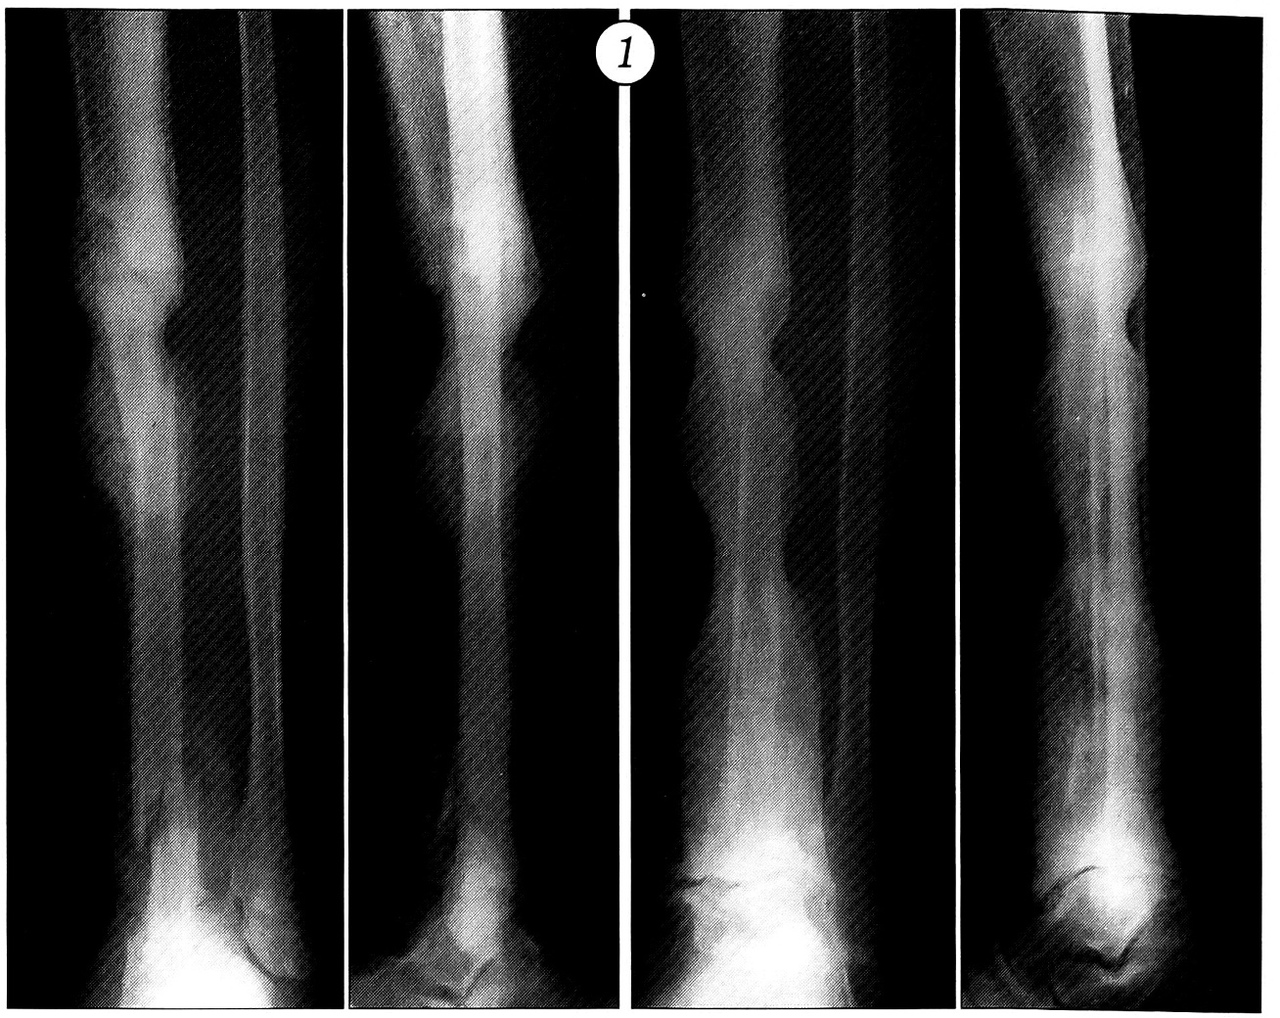

Наши многолетние наблюдения показали, что диафизарным отделом малоберцовой кости с питающим ее сосудистым пучком можно замещать обширные дефекты бедра, большеберцовой, плечевой кости и костей предплечья. После приживления трансплантат под действием функциональной нагрузки утолщается, приближаясь по размерам и форме к кости, дефект которой им замещается (рис. 1). Особенно показана такая тактика при больших дефектах костей предплечья и плеча любого генеза в сочетании с плохой васкуляризацией тканей, а также при врожденных ложных суставах (рис. 2).

Рис. 1. Этапы адаптационной перестройки васкуляризованного аутотрансплантата из малоберцовой кости через периодически возникающие стресс-переломы при замещении обширного дефекта большеберцовой кости после удаления опухоли.